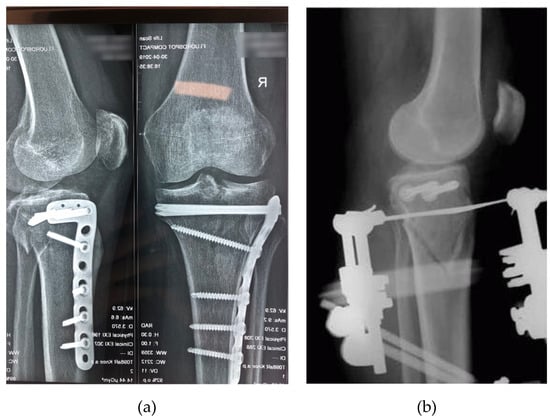

- Internal fixation (Figure 2a), which restores bone physiology and enable early mobilization of the limb. The function of the injured bones can be restored and full support for physiological load is ensured by applying internal fixation. The vast majority of internal fixation systems are manufactured from stainless steel or titanium. A review of internal fixation systems and the fracture sites for which they are suitable can be found in [18] and [19]. By means of internal fixation, malunion is a very rare occurrence and mobilization of the patient is very fast. Internal fixation systems have disadvantages, however. The stiffness and Young modulus of the implant material are much higher than in the case of cortical tissue of the human bone. Fixation of the bone fragments with high rigidity materials prevents load transfer to the healing bone, which is unfavorable for fracture callus remodeling [20]. The necessity of surgical removal after the bone healing is another trauma the patient has to undergo.

- External fixation (Figure 2b) is considered flexible fixation. External fixator systems consist of elements such as pins, wires (Schanz screws, Steinman pins, Kirschner wires) and belts that are conventionally used as a dynamic fixation of fractured bones. External fixation approach is used for open fractures with massive soft-tissue injuries such as open Type II, Type III fractures (Type II and III are open fractures with a soft tissue laceration larger than 1 cm and 10 cm respectively, minor and severe comminution respectively and with simple and complex fracture pattern, respectively) and even in articular fractures, in which the surgical trauma to the limb during fixation is reduced [18].